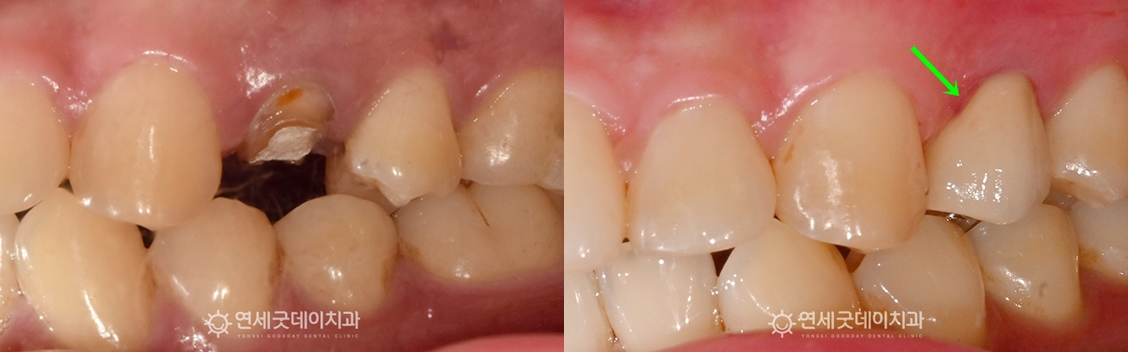

치아파절 재신경치료 전후 구내모습 비교

▲ 치아파절 치료전후 비교

(2025년 8월 / 2025년 10월)

치아파절 부위는 원래 치아의 모양으로 외형이 복구되었으며

자연치아를 보다 오래 보존할 수 있게 되었습니다.